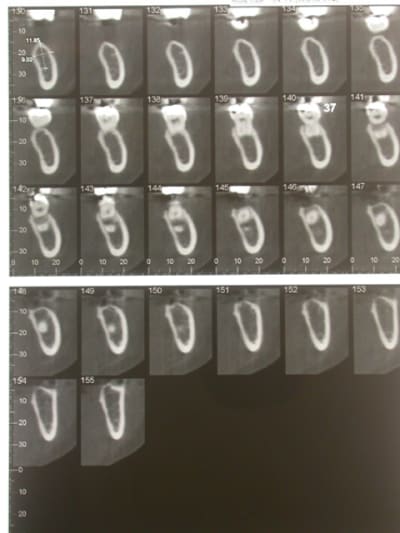

La consoeur m'a envoyé ça aussi, à priori la crête n'était pas très fine.

on dirait que sous la corticale il n'y a pratiquement pas de spongieux,ca peut peut etre venir d'un forage excessif

qu'en pensent les pros